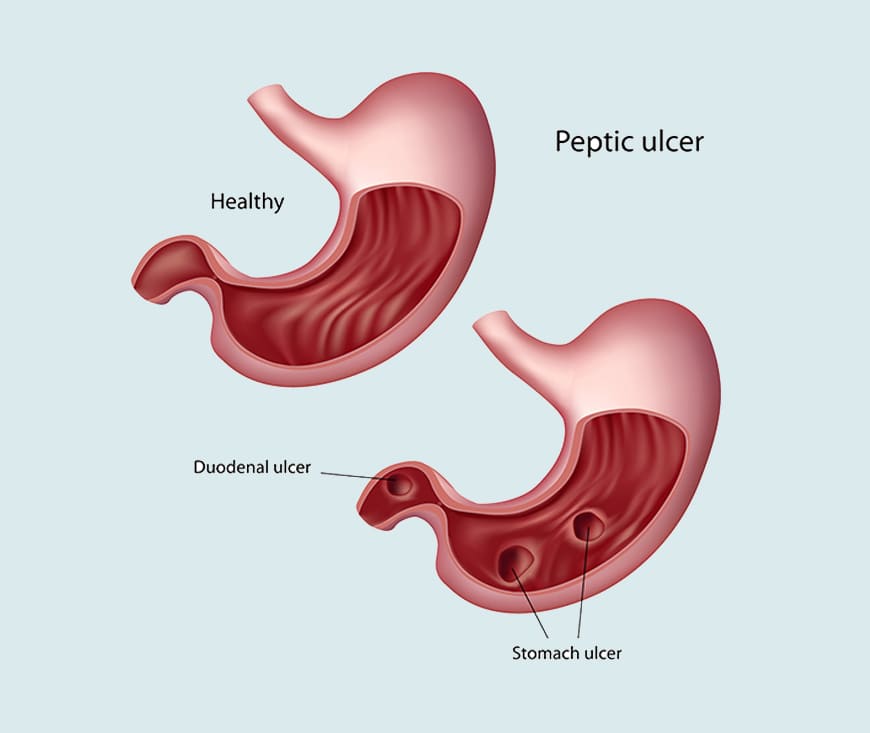

Acidity, or acid reflux, occurs when stomach acid backs up into the esophagus, causing discomfort or a burning sensation. Treatment includes antacids, proton pump inhibitors, and H2 blockers to reduce stomach acid. Lifestyle changes like avoiding spicy foods, eating smaller meals, and managing stress can help. Regular medical check-ups are important for chronic cases.

Abdominal pain can result from various causes, such as indigestion, gas, infections, or

more serious conditions like ulcers or appendicitis. Treatment depends on the cause and

may include pain relievers, antibiotics, or dietary changes. If the pain is severe or

persistent, it's important to seek medical attention for proper diagnosis and treatment.

Duodenal ulcer treatment focuses on reducing stomach acid and promoting healing. Medications like proton pump inhibitors (PPIs) or H2 blockers help reduce acid production. Antibiotics may be prescribed if the ulcer is caused by *Helicobacter pylori* infection. Antacids and lifestyle changes, such as avoiding spicy foods and reducing stress, can also aid in recovery.